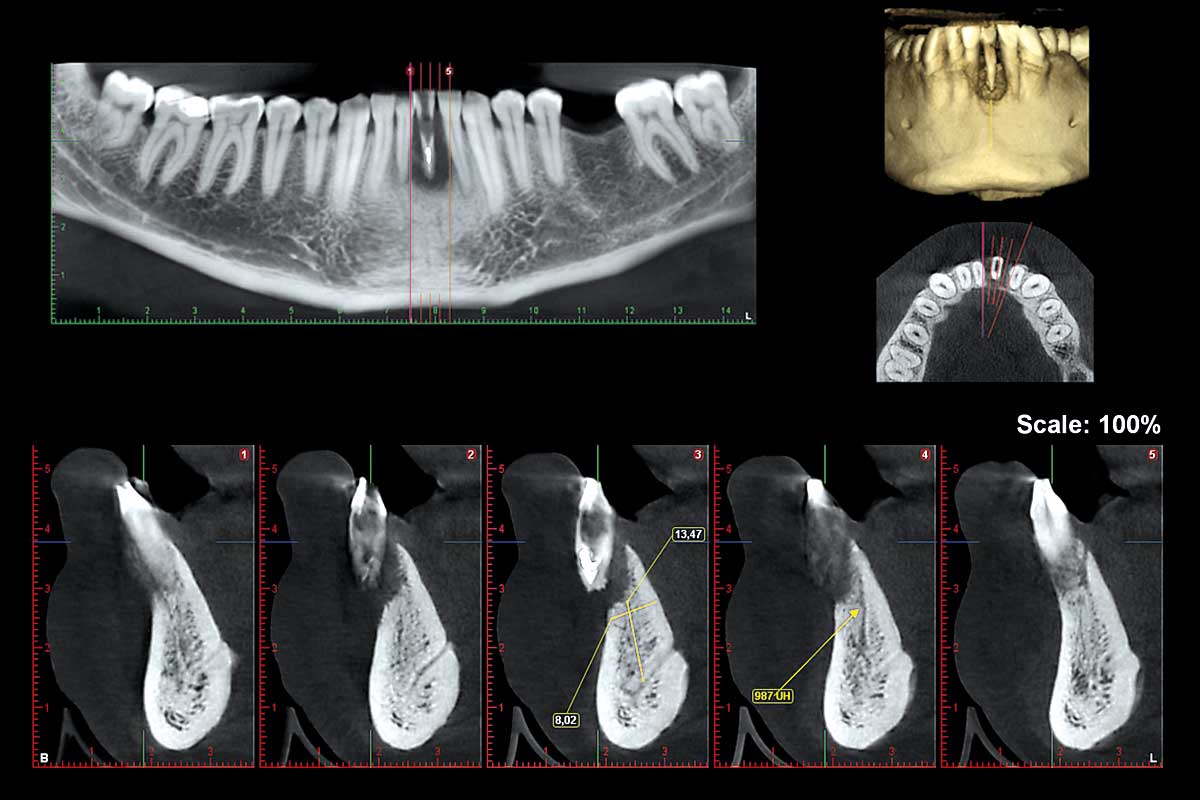

A patient presented with severe gingival recession and pronounced inflammation affecting tooth #24. Following extraction of the tooth and thorough debridement of the infected site, a complete loss of the vestibular wall and a slight resorption of the lingual wall were identified. In this situation, NOVAMag® membrane was cut to shape and given a suitable convexity and used as a rigid plate and fixated with two resorbable NOVAMag® fixation screws. The membrane was fixated of the lingual side only in this case. A narrow ⌀ 3.2 × 13 mm implant was placed. The remaining peri-implant gaps were filled with maxgraft® granules, and the augmentation site was finally covered with a collprotect® membrane.

Follow-up CBCT scans taken at 4 and 9 months demonstrated stable bone regeneration and preservation of the ridge contour in its natural form on the buccal side where the membrane was placed. Deeper placement of the implant initially would have been better. Satisfactory closure of the initial gingival recession was achieved despite minimal mucogingival intervention.